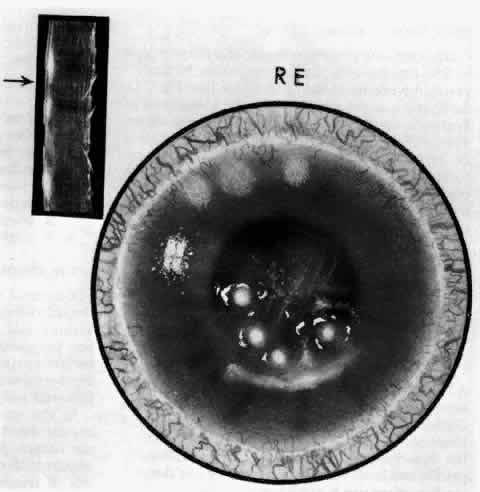

of the eye. A posterior scleritis often occurs as an extension of anterior

disease; but, as in Figure 20, most of the inflammation (in some cases all of the inflammation) is in

the posterior segment and the exudative detachments and subretinal granulomas

Fig. 20. Posterior scleritis. This eye was removed because of loss of vision and

pain, mistakenly diagnosed as malignant melanoma. (Courtesy of Professor N. Ashton) Fig. 20. Posterior scleritis. This eye was removed because of loss of vision and

pain, mistakenly diagnosed as malignant melanoma. (Courtesy of Professor N. Ashton)

|